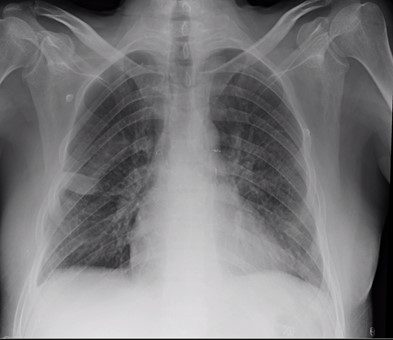

Een COVID-19-patiënt op intensieve zorg met onherstelbaar beschadigde longen kreeg op 1 januari 2021 nieuwe longen in het transplantatiecentrum van UZ Leuven. Het is de eerste keer in de Benelux dat een persoon die verzorgd wordt op een intensieve COVID-19-afdeling een longtransplantatie krijgt.

Op 1 januari 2021 kreeg een patiënt die aan die strenge criteria voldeed een longtransplantatie in UZ Leuven. Zijn familie moest de toestemming geven voor de transplantatie, aangezien de persoon zelf in coma lag. De transplantatie is goed verlopen en de patiënt, die ondertussen het ziekenhuis kon verlaten, stelt het goed. Een week later kreeg ook een tweede patiënt van een intensieve COVID-afdeling nieuwe longen.

Verwacht wordt dat de dringende longtransplantaties bij COVID-19-patiënten minder dan 5% van het totale aantal longtransplantaties zullen uitmaken. De kans op overleven 1 jaar na de longtransplantatie is normaal gezien 90%, bij de urgente longtransplantaties bij intensieve COVID-19-patiënten kan dat dalen tot 50% . Het transplantatiecentrum van UZ Leuven doet gemiddeld 70 longtransplantaties per jaar. De transplantatieartsen verwachten de komende maanden en jaren trouwens meer vraag naar longtransplantaties bij patiënten die een ernstige COVID-19-infectie hebben doorgemaakt. Dergelijke patiënten zullen dan wel in de normale longtransplantatietrajecten terechtkomen.